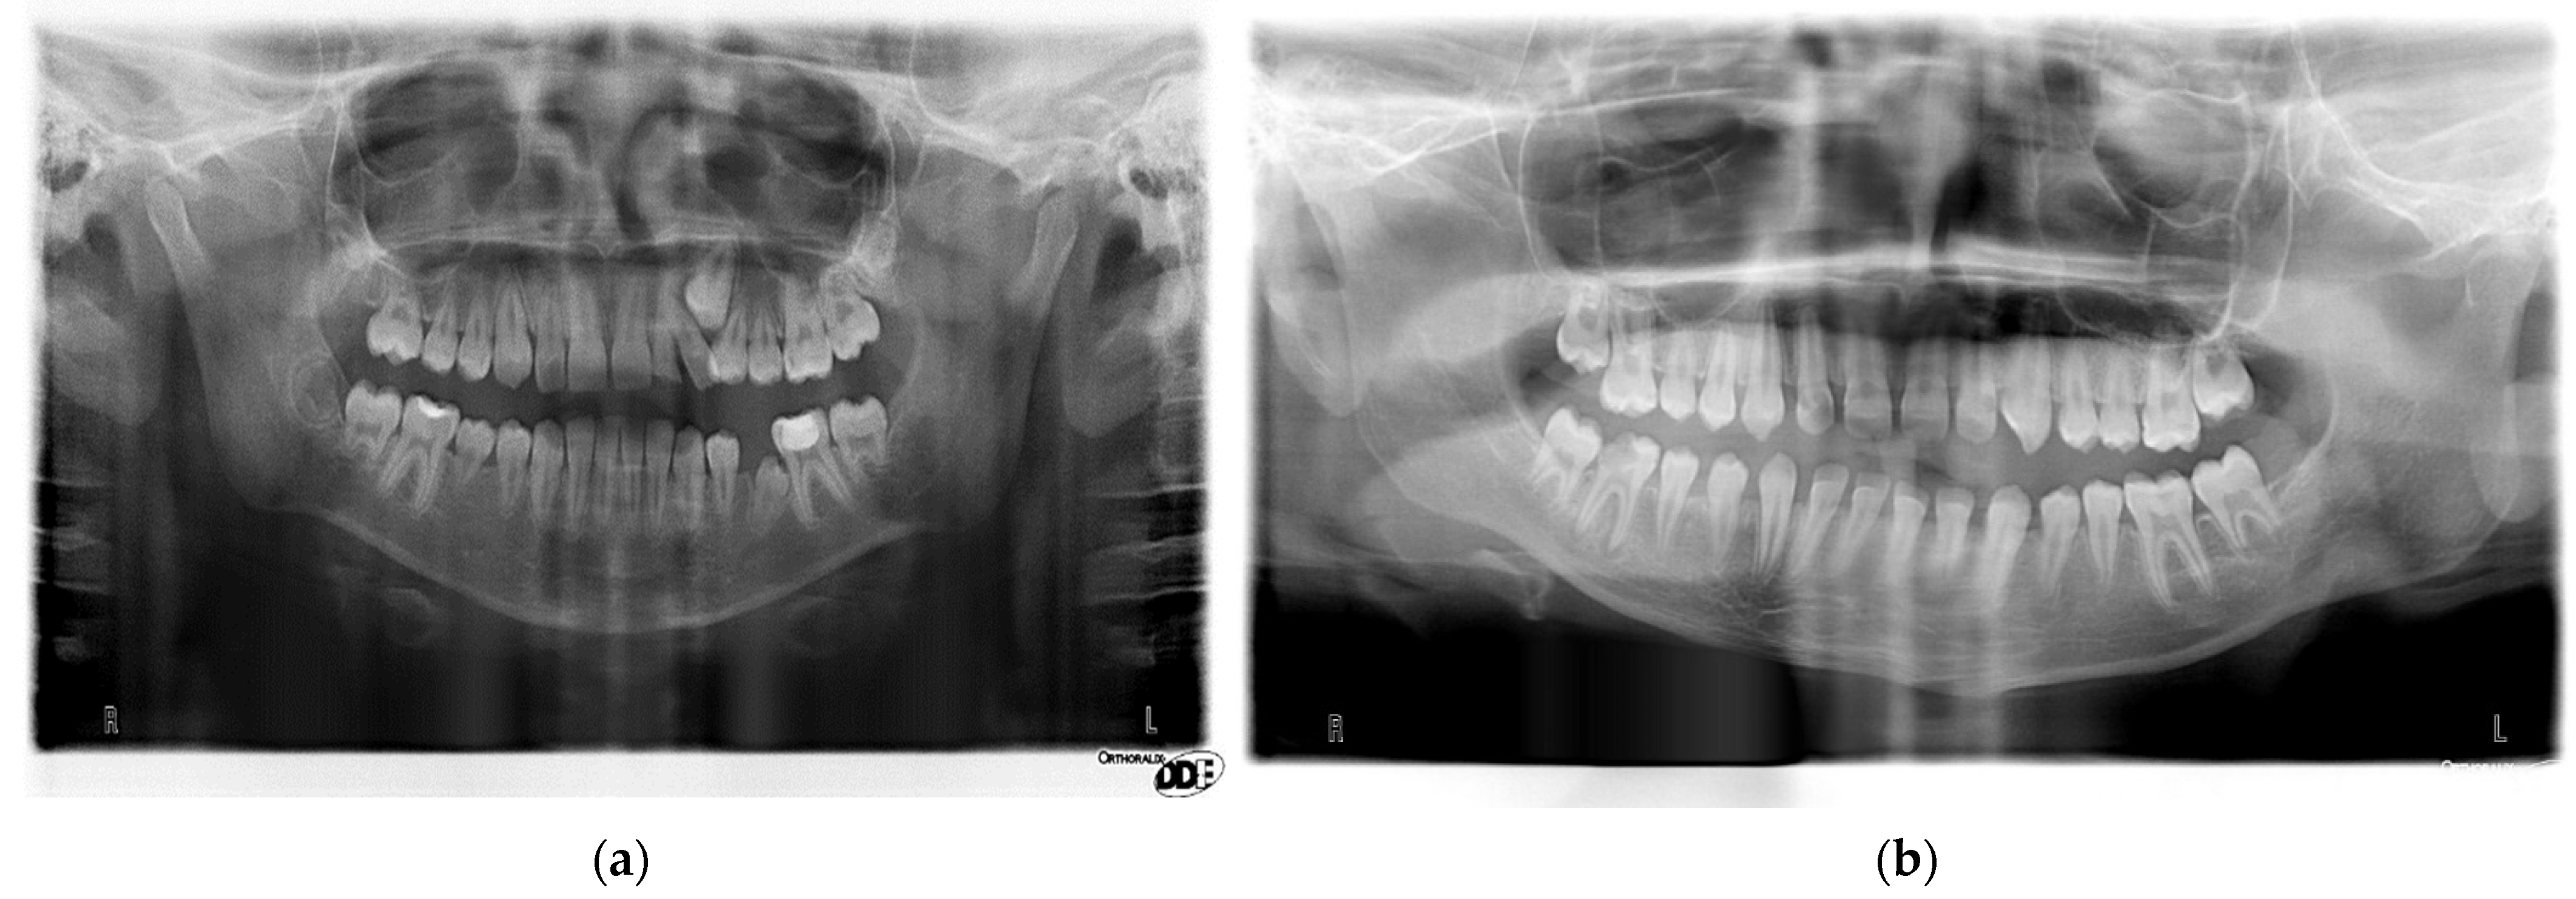

2. Materials and Methods

2.1. Study Group Description

2.2. Orthodontic Assessment in Both Groups

2.3. Assessment of Dental Anomalies and Dental Age in Cancer Group